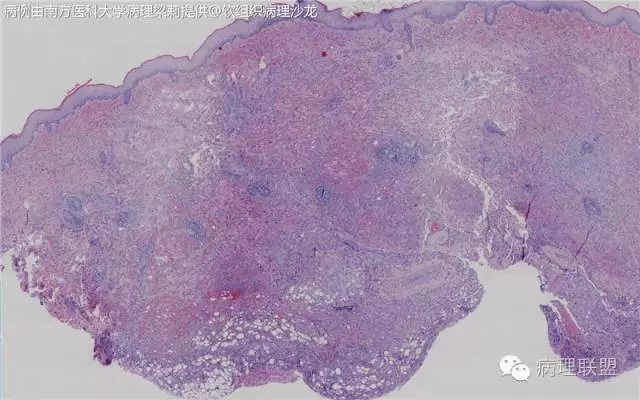

新生儿,男,14天。生后发现右前臂暗红色肿物14天。术中见:肿物2x1.5cm,深达筋膜下及肌膜表面,暗红色血管样。(南方医科大学病理梁莉提供 致谢!)

这例我们发的是卡波西样血管内皮细胞瘤,考虑如下:(1)新生儿,肢体肿物;(2)位置深,侵及皮下脂肪;(3)大多是裂隙状血管,也有少量吻合的血管网,细胞有异形,可见坏死

Kaposi型血管内皮瘤常有隐约小叶结构,梭形细胞束间有毛细血管,细胞核异型性和分裂活性一般不明显,常见梭形细胞束和圆形"肾小球样"实性细胞巢混合存在。

而复合性血管内皮瘤则是由良性、中间性和恶性的成份组成,也是浸润性生长,常常侵犯皮下脂肪组织,此例细胞形态由梭形细胞、卵圆形细胞及上皮样细胞组成,形态可见良性区域、中间性区域及高分化血管肉瘤或上皮样血管肉瘤区域,因此,似乎复合性血管内皮瘤更妥。此类肿瘤可以发生于婴幼儿。当然与Kaposi型血管内皮瘤一样,同属中间性血管瘤,只是后者,若肿瘤体积大,可出现Kasabach-Merritt综合征。